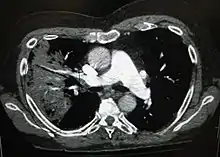

صورة بالأبيض والأسود تُظهر الأعضاء الداخلية في مقطع عرضي كما تظهرها الأشعة المقطعية. حيث يتوقع المرء أن يكون الأسود على الجانب الأيسر نشاهد منطقة أكثر بياضًا مع خطوط سوداء بداخلها.

كثيرًا ما يتم استخدام التصوير الشعاعي للصدر في التشخيص.[15] عند الأشخاص المصابين إصابة طفيفة، يُطلب التصوير فقط في الحالات التي من المرجح أن يحدث لديها مضاعفات أو التي لم تتحسن مع العلاج أو التي لم يتم التأكد من سبب إصابتها.[15][41] أما إذا كان الشخص مريضا بدرجة كافية تتطلب دخوله إلى المستشفى، فيُوصى بإجراء تصوير شعاعي للصدر.[41] علما أن النتائج لا ترتبط دومًا بخطورة المرض ولاتفرق تفريقا موثوقا به بين العدوى البكتيرية والعدوى الفيروسية.[15]

يمكن تصنيف ظواهر ذات الرئة التي تظهر في التصوير الشعاعي باعتبارها ذات الرئة الفصي وذات الرئة القصبي (والمعروف كذلك باسم ذات الرئة الفصيصي) وذات الرئة الخلالي.[44] يتصف المظهر الكلاسيكي لذات الرئة البكتيري المكتسب من المجتمع تصلد الرئة في فص رئوي قطعي واحد يعرف باسم ذات الرئة الفصي.[24] ولكن قد تختلف النتائج وتشيع أنماط أخرى في أنواع أخرى من ذات الرئة.[24] قد يظهر ذات الرئة الشفطي عتامات ثنائية الجانب في قاعدتي الرئتين وفي الجانب الأيمن.[24] وقد تظهر الصور الشعاعية لذات الرئة الفيروسي طبيعية أو مفرطة الانتفاخ أو بها مساحات مرقعة ثنائية الجانب أو تظهر مشابهة لذات الرئة البكتيري مع التكثف الفصي.[24] قد لا تكون هناك موجودات شعاعية في المراحل المبكرة من المرض، خاصةً في وجود الجفاف؛ أو ربما يصعب تفسيرها عند أولئك الذين يعانون من السمنة أو لديهم تاريخ مرض رئوي.[16] يمكن أن تُعطي الأشعة المقطعية معلومات إضافية في الحالات غير المحدّدة.[24]